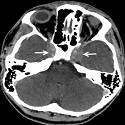

Anévrysme de la veine de Galien révélé à l’âge adulte

Badreeddine Alami, Mustapha Maaroufi

PAMJ. 2014; 19: 102. Published 29 September 2014